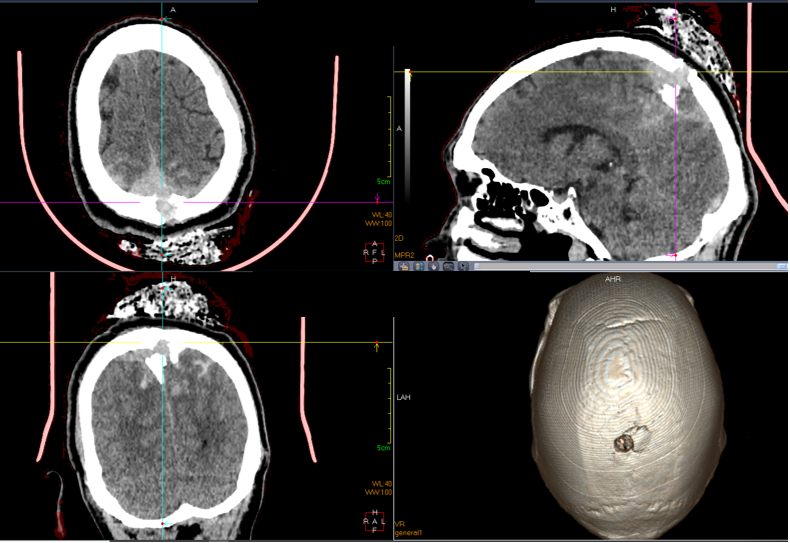

在呼啸的120急救声中,58岁的建筑工人老刘被送入我院抢救室。老刘在两小时前被10米高处掉落的钢筋扎破头部,钢筋直径约1cm,当时佩戴的安全帽被刺破,径直插入颅脑。入抢救室时钢筋已被取出,头部用纱布进行了压迫止血处理。急查头颅CT显示:顶骨骨折,颅内碎骨片及气颅,硬脑膜外及下血肿,脑挫裂伤。虽然患者入院时神志清楚,但是钢筋正好刺入矢状窦,有大块骨折片刺入矢状窦,存在随时可能大出血的危险,病情十分危急。

头颅CT提示颅内碎骨片、脑挫裂伤,钢筋刺入矢状窦